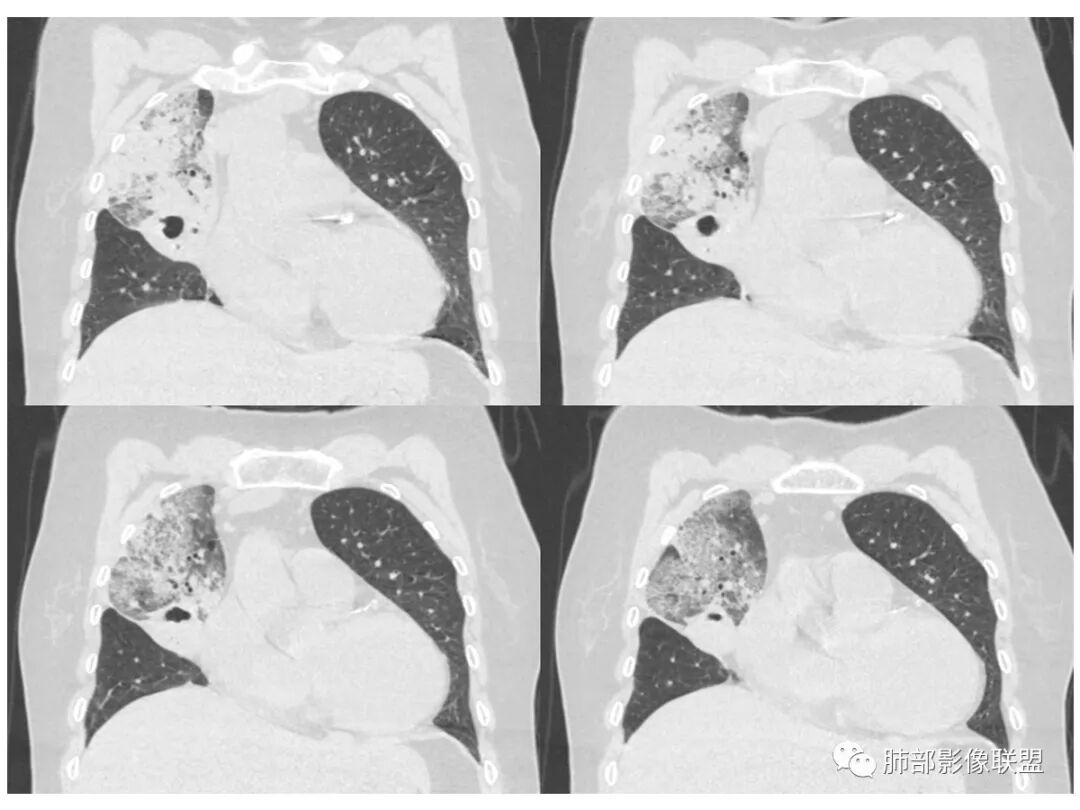

老年女性,右肺上叶大片实变及磨玻璃密度影,磨玻璃边缘清晰,内可见小叶间隔增厚,内可见空洞,似可见分隔,叶间裂局部膨隆,纵膈窗,没有增强,枯树枝不明显,肺炎型肺癌可能,鉴别大叶性肺炎,结核?

胸CT:右肺上叶实变内可见支气管充气征,近端支气管狭窄,远端扩张,周围可见毛玻璃影,右肺中叶支气管闭塞,并可见气道壁钙化,右肺中叶体积缩小,实变内可见空洞,并可见气液平面,空洞周围可见毛玻璃样影,右肺下叶支气管开口狭窄,右肺门淋巴结肿大。纵隔窗可见病灶与壁层胸膜间隙增宽,考虑良性病变-----感染性病变------TB?

1.右上肺大片状影,周围有磨玻璃影,支气管截断征、枯枝征、远端支气管充气征,可见多个大小不等囊泡(支气管阻塞活瓣作用形成),病灶有少许收缩力感,叶间裂被稍牵拉内移;

主动脉弓旁有个增大淋巴结,稍圆鼓,但似乎有点钙化,右上肺病变外周也有少许钙化,肺炎性肺癌可以外周有钙化的

老年女性,慢性病程,咳嗽伴白色粘液痰,无发热腹痛,糖尿病,白细胞及C反应蛋白不高,血沉快,铁蛋白高。胸部CT,右肺上叶大片状实变伴磨玻璃密度影,边界不清,边缘局部膨隆,叶裂弧形下坠,实变影宽基底与胸膜相贴;右肺下叶前基底段见类似病灶;右肺中叶不张并空洞形成,空洞内见气液平面;综合考虑右肺上叶及下叶肺炎型肺癌,右肺中叶结核。

这里是中叶的不张和空洞,有钙化,结核确实也不能排除

主病灶应该是粘腺腺癌,右中叶不张?,内空洞,壁光滑,考虑感染

3.熊老师告诉我们:肺结核可以有磨玻璃,这个我以前一直不知道,右肺门淋巴结有钙化,病灶内纵膈窗隐约细细点状钙化,所以结核磨玻璃可以,

中叶的体积缩小,也不是粘液腺癌能完全解释,